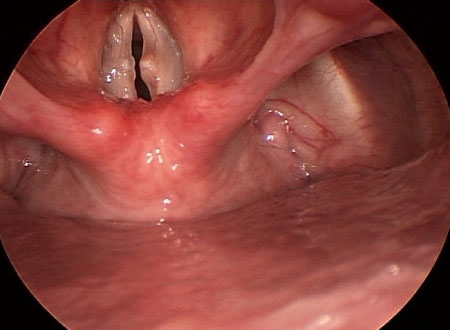

Laringite por refluxo[Figure caption and citation for the preceding image starts]: Laringite por refluxoDo acervo da University of Wisconsin School of Medicine and Public Health [Citation ends].

Secundária a refluxo laringofaríngeo.

Pode complicar-se em decorrência da formação de granuloma nas pregas vocais, aspiração, laringoespasmo e estenose subglótica.[9]